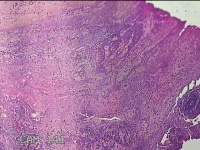

宫颈6点、10点、12点组织

性别

女

年龄

30岁

临床诊断

女性盆腔炎;宫颈炎性疾病;异常子宫出血

一般病史

宫颈HPV-56(+),TCT见非典型鳞状上皮细胞

标本名称

大体所见

1.“宫颈6点组织”:灰白暗红色不规则组织0.5x0.3x0.2cm一块。 2.“宫颈10点组织”:灰白暗红色不规则组织0.3x0.2x0.1cm一块。 3.“宫颈12点组织”:灰白暗红色不规则组织0.8x0.5x0.3cm两块。

所提供图片不具有诊断价值。

CIN1